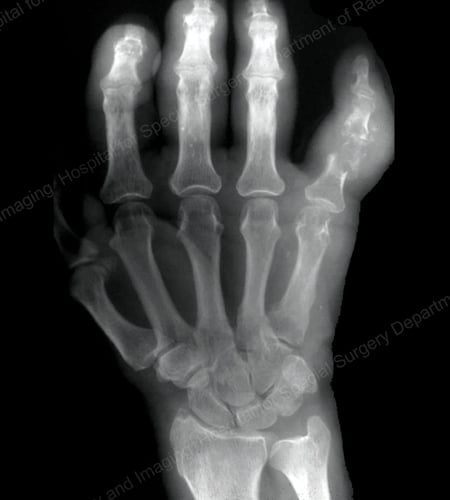

X-rays are the standard imaging technique for gout (See Figures 12-17: Figure 12: Gout of the Base of the 1st Toe; Figure 13: Gout of the Distal Finger Joints; Figure 14: Gouty Change and Soft Tissue Calcification About the Base of the 1st Toe; Figure 15: Gouty Destruction at Multiple Finger Joints; Figure 16: Gouty Erosion at the Proximal Ulna at the Elbow; Figure 17: Large Tophus Seen as Soft Tissue Mass at the Elbow) but in special cases, such as when gout needs to be separated from infection or tumor, magnetic resonance imaging (MRI) (Figure 18: MRI of the Knee Showing Gouty Soft Tissue Mass and Erosion of the Kneecap) or ultrasound (Figure 19: Power Doppler Study Showing Gouty Inflammation at the Base of the 1st Toe) will be helpful. A newer technique called a dual-energy CT scan (DECT) can show urate crystals in green color.

X-ray of gouty destruction at multiple finger joints

Figure 15: Gouty Destruction at Multiple Finger Joints